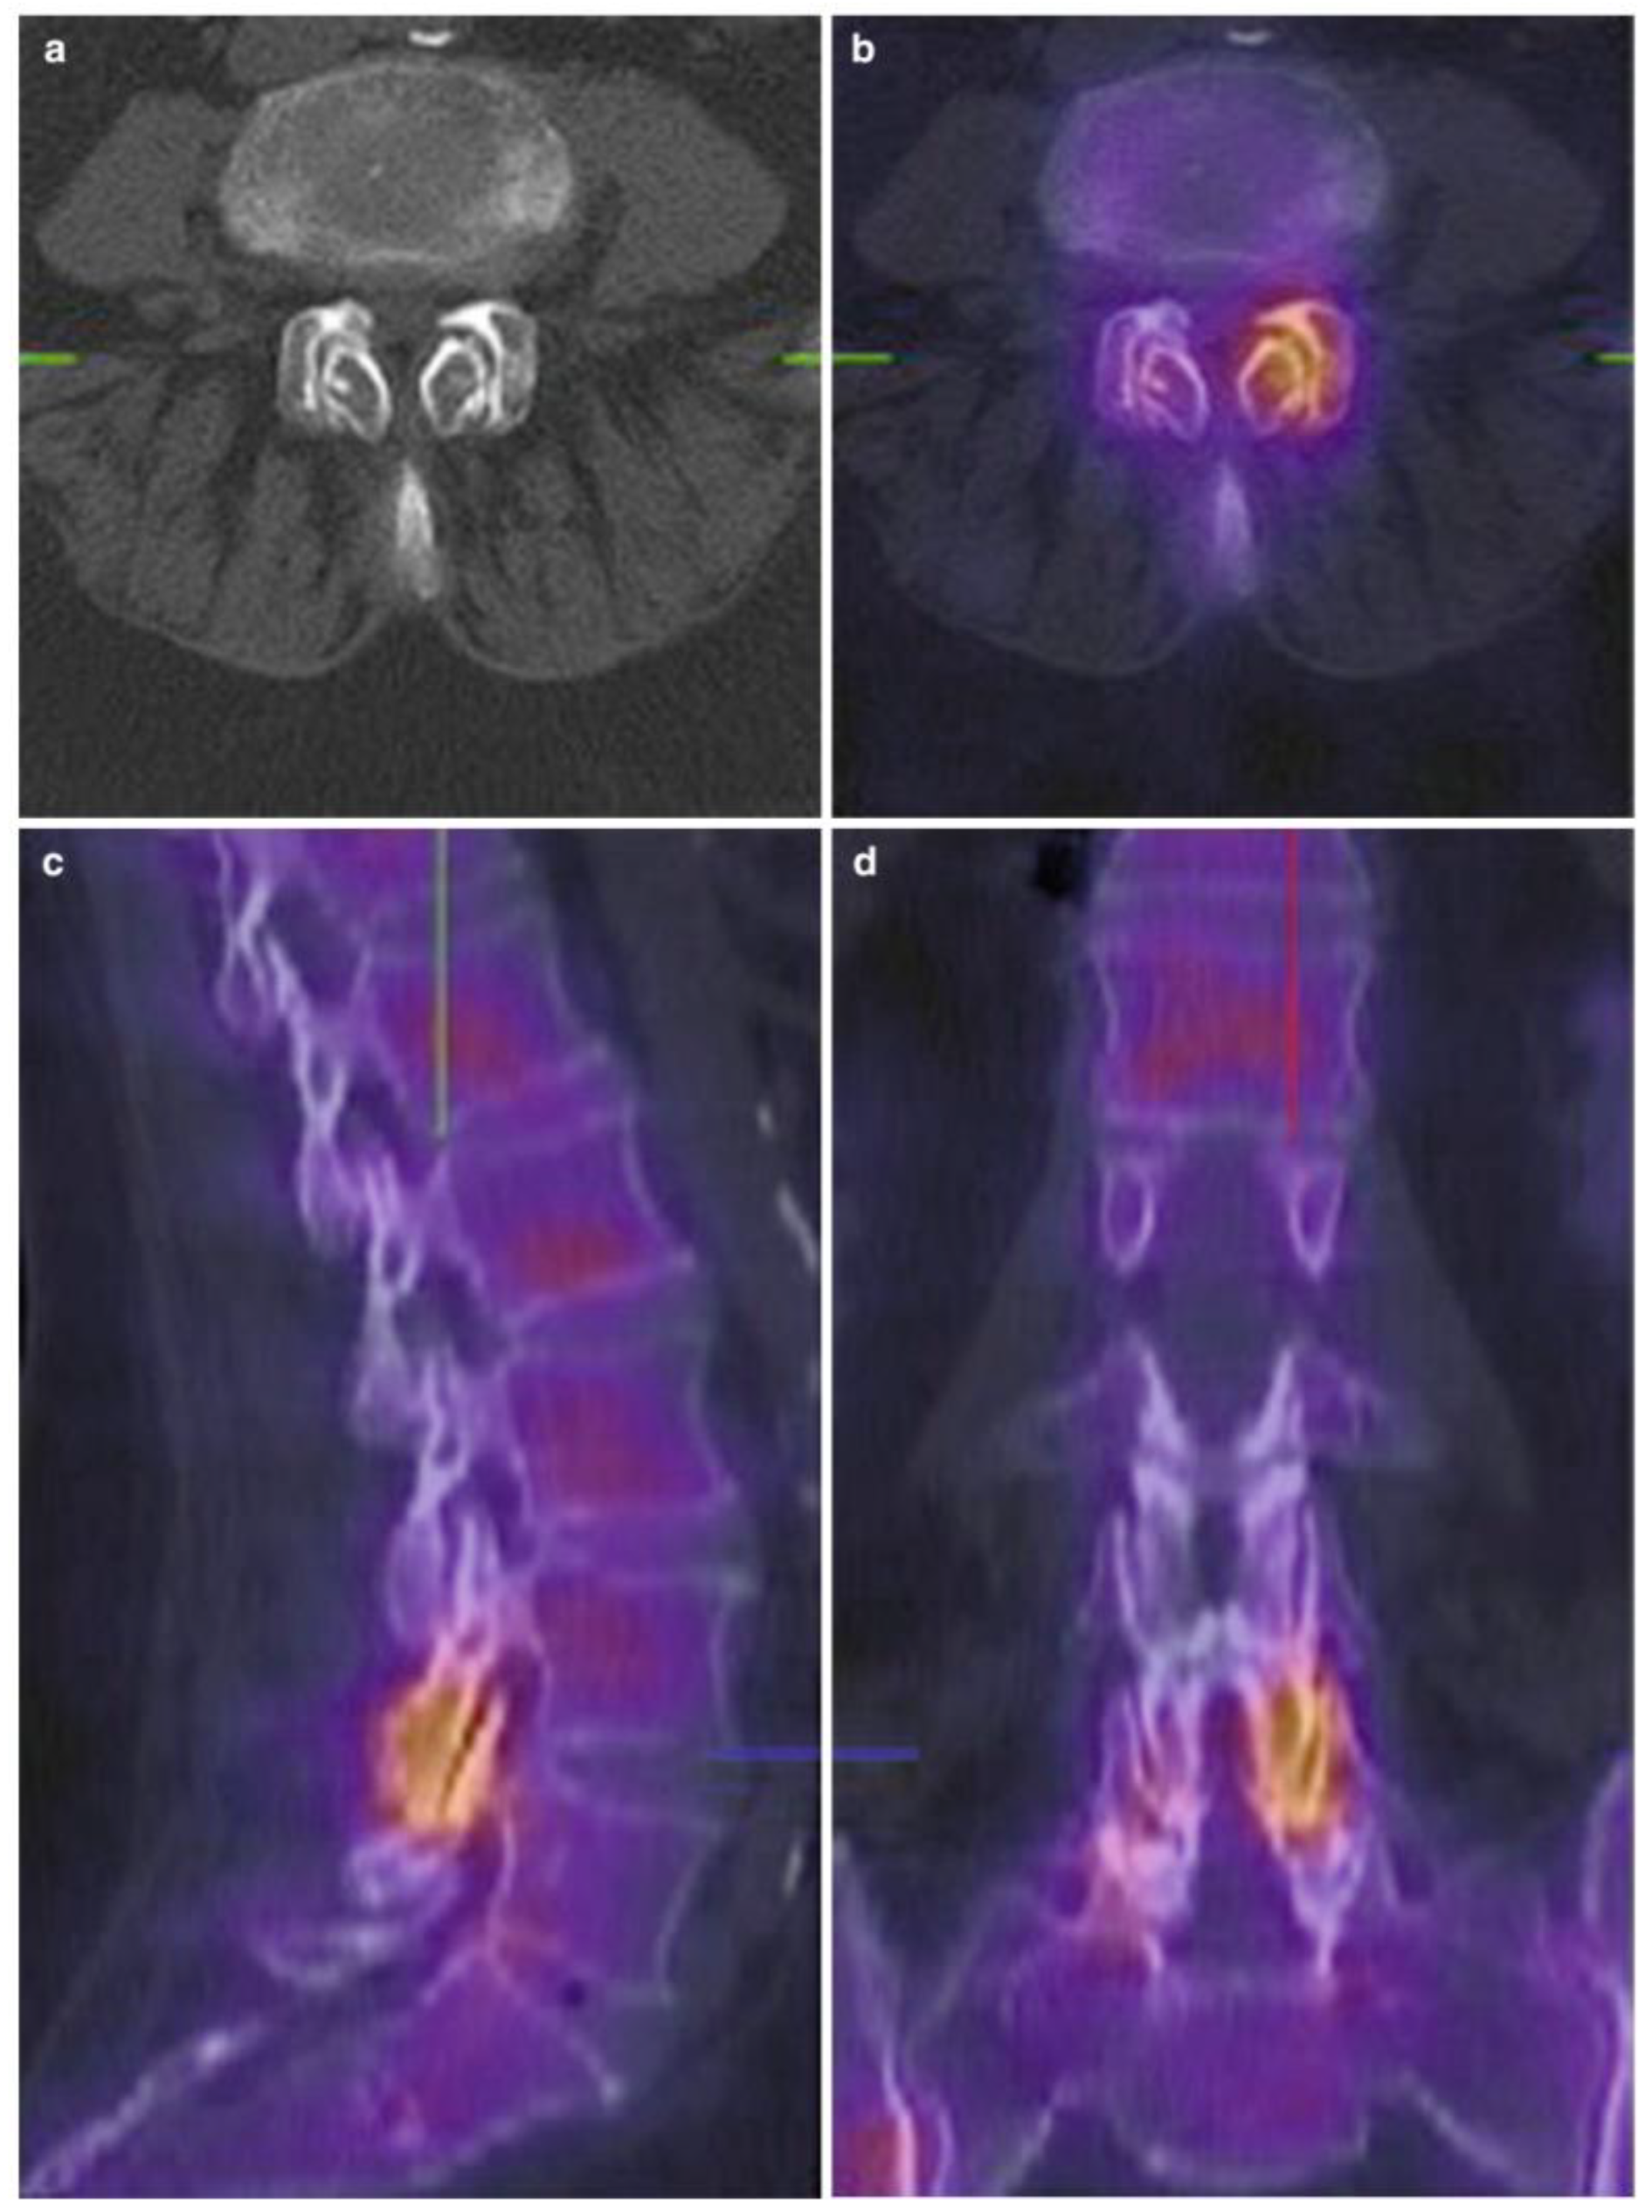

5.4. Single-Photon Emission Computed Tomography-CT (SPECT-CT)

- Van de Kelft, E.; Verleye, G.; Van de Kelft, A.S.; Melis, K.; Van Goethem, J. Validation of Topographic Hybrid Single-Photon Emission Computerized Tomography with Computerized Tomography Scan in Patients with and without Nonspecific Chronic Low Back Pain. A Prospective Comparative Study. Spine J. 2017, 17, 1457–1463. [Google Scholar] [CrossRef] [PubMed]

- Matar, H.E.; Navalkissoor, S.; Berovic, M.; Shetty, R.; Garlick, N.; Casey, A.T.H.; Quigley, A.-M. Is Hybrid Imaging (SPECT/CT) a Useful Adjunct in the Management of Suspected Facet Joints Arthropathy? Int. Orthop. 2013, 37, 865–870. [Google Scholar] [CrossRef]

- Freiermuth, D.; Kretzschmar, M.; Bilecen, D.; Schaeren, S.; Jacob, A.L.; Aeschbach, A.; Ruppen, W. Correlation of 99mTc-DPD SPECT/CT Scan Findings and Diagnostic Blockades of Lumbar Medial Branches in Patients with Unspecific Low Back Pain in a Randomized-Controlled Trial. Pain Med. 2015, 16, 1916–1922. [Google Scholar] [CrossRef]

- Pneumaticos, S.G.; Chatziioannou, S.N.; Hipp, J.A.; Moore, W.H.; Esses, S.I. Low Pain: Prediction of Short-Term Outcome of Facet Joint Injection with Bone Scintigraphy. Radiology 2006, 238, 693–698. [Google Scholar] [CrossRef]